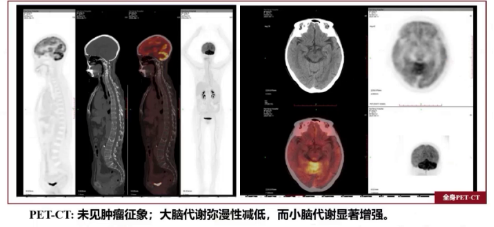

因患者高龄消瘦,脾大、外院骨髓涂片偶见噬血现象,CA125升高,为寻找肿瘤线索进行全身PET/CT检查,虽未见肿瘤征象,但发现大脑代谢弥漫性降低,小脑代谢显著增强,考虑有可疑脑膜炎症,存在自身免疫性脑炎、颅内感染可能。

image.png